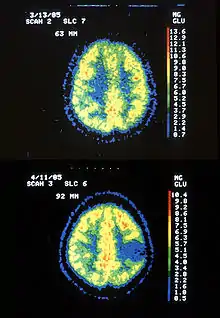

| Two PET images—the upper of which shows a normal brain and the lower shows astrocytoma | |